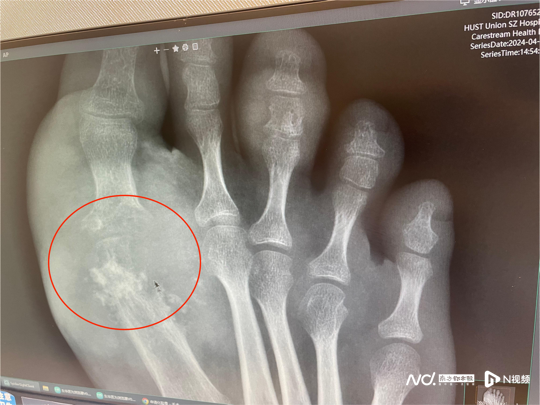

第一跖趾关节(即大脚趾与足部连接的关节)也是痛风石喜欢积存的区域。(南都资料图片)